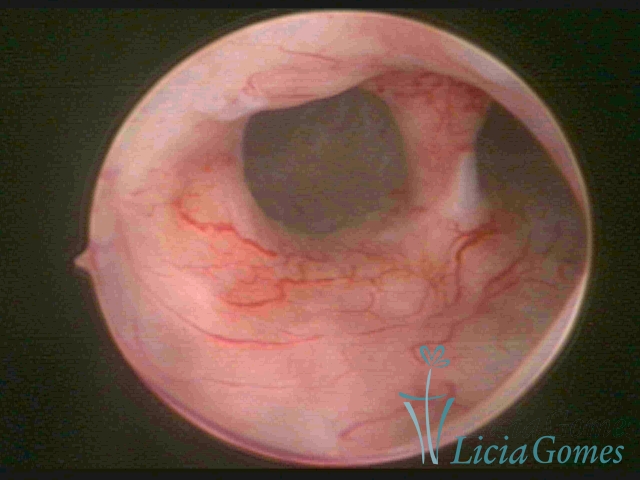

Uterus didelphys

The presence of two uterine cervices and a double vagina, similar to unicornuate uteri, with a normal covering of endometrium.